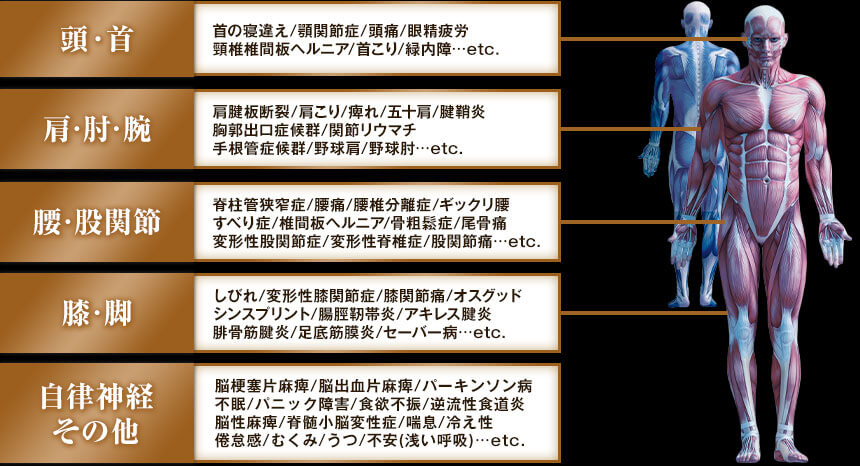

| 頭・首 | 首の寝違え 顎関節症 頭痛 眼精疲労 頸椎椎間板ヘルニア 首こり 緑内障…etc. |

|---|---|

| 肩・肘・腕 | 肩腱板断裂 肩こり 痺れ 五十肩 腱鞘炎 胸郭出口症候群 関節リウマチ 手根管症候群 野球肩 野球肘…etc. |

| 腰・股関節 | 脊柱管狭窄症 腰痛 腰椎分離症 ギックリ腰 すべり症 骨粗鬆症 椎間板ヘルニア 尾骨痛 変形性股関節症 変形性脊椎症 股関節痛…etc. |

| 膝・脚 | しびれ 変形性膝関節症 膝関節痛 オスグッド シンスプリント 腸脛靭帯炎 アキレス腱炎 腓骨筋腱炎 足底筋膜炎 セーバー病…etc. |

| 自律神経 その他 |

脳梗塞片麻痺 脳出血片麻痺 パーキンソン病 不眠 パニック障害 食欲不振 逆流性食道炎 脳性麻痺 脊髄小脳変性症 喘息 冷え性 倦怠感 むくみ うつ 不安(浅い呼吸)…etc. |